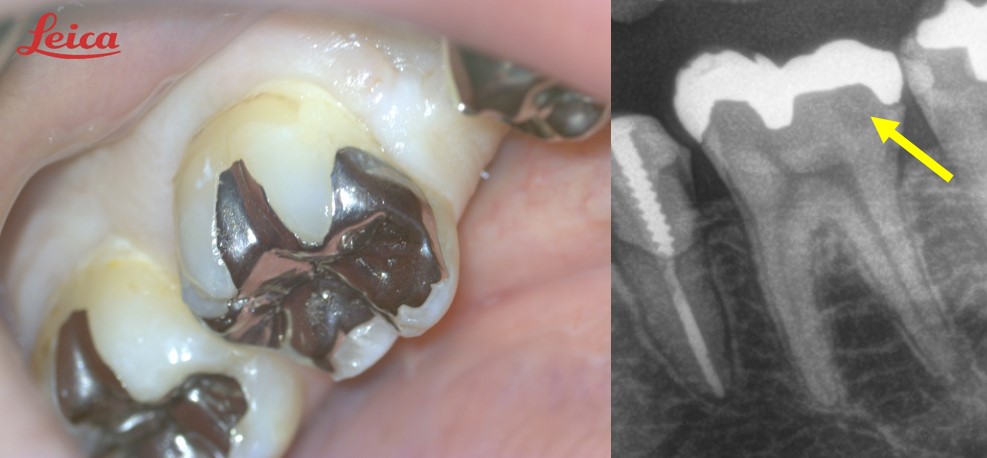

深いむし歯 神経残す 間接覆髄法 (都内港区内幸町新橋虎ノ門日比谷霞ヶ関歯科歯医者)

内幸町間接覆髄法 MTA 深いむし歯神経を残す治療 都内港区新橋内幸町新橋虎ノ門霞ヶ関日比谷